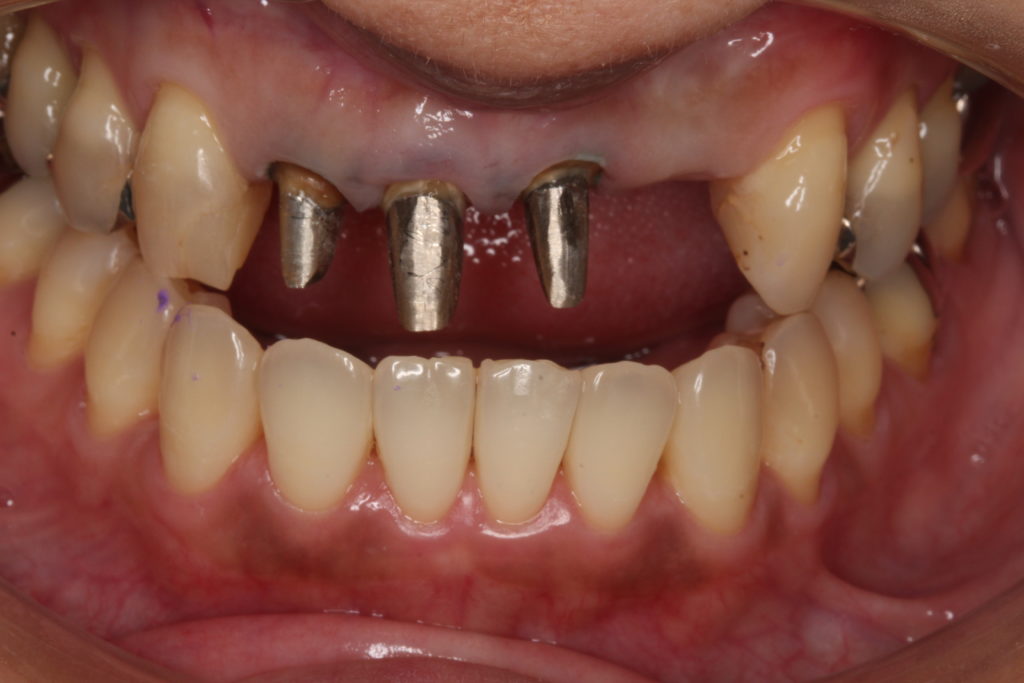

お口の中を見てみると、

このような状態です。

前歯の4本がぶせ物で治療がされています。

こちらの4本ですね。

20年以上まえの治療で、歯が黄色く黄ばんで、歯の根元が黒くなっている箇所もあります。

こちらは「レジン前装冠」というかぶせ物で、表面の見える所はレジンというプラスティック樹脂で、内部から裏側には金属が使われています。